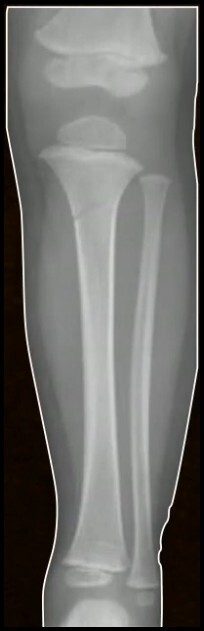

Q

FX Tíbia Proximal

Tipos de fratura (4)

A

1. Espinha tibial

2. Tuberosidade da Tibia

3. Fisária

4. Metafisária

15

Característidas FX Metafisária (3)

• 2 - 8 anos

• Valgo + Extensão

• Grandes desvios são incomuns

FX DE COZEN